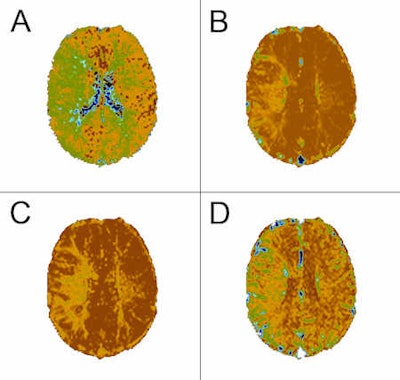

These six images show a comparison between contrast-enhanced perfusion and non-contrast perfusion using arterial spin labeling technique in a 34-year-old male with a chronic obliteration of the right middle cerebral artery. In the set of four contrast-enhanced perfusion images, A = time-to-peak (TTP), B = relative cerebral blood volume (CBV), C = relative mean transit time (MTT), D = relative cerebral blood flow (CBF). The other two are pulsed arterial spin labeling (QUIPPS II sequence) images. A: Sample of source data, signal in the circular region placed in the left hemisphere is 102% of that in the right. B: Relative cerebral blood flow, signal in the circular region placed in the left hemisphere is 271% of that in the right. Image courtesy of Dr. Josef Vymazal.ASL has found application in many research and clinical areas. One area that has received much attention is in the evaluation of patients with cerebrovascular disease, both in the initial assessment of perfusion as well as in evaluating treatment response. Vymazal believes the greatest limitation of these techniques may be that MRI is often not the preferred investigative method in acute situations. In non-emergency settings, however, ASL has the benefit of not only being a powerful, noninvasive perfusion imaging method, but also that it allows the investigative physician access to the many other high quality soft-tissue imaging techniques that can be applied in the MRI setting.